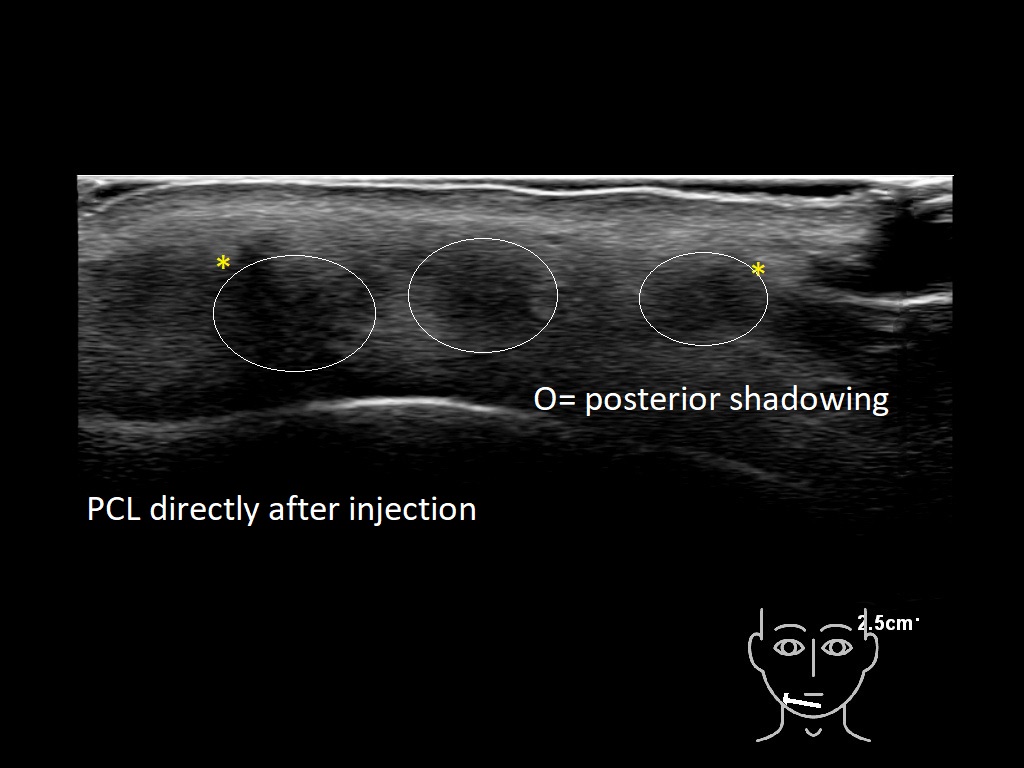

Fillers

Draw in the second image below where the fillers are located. To check if your answer is correct, swipe the first image to the right.

PCL 0